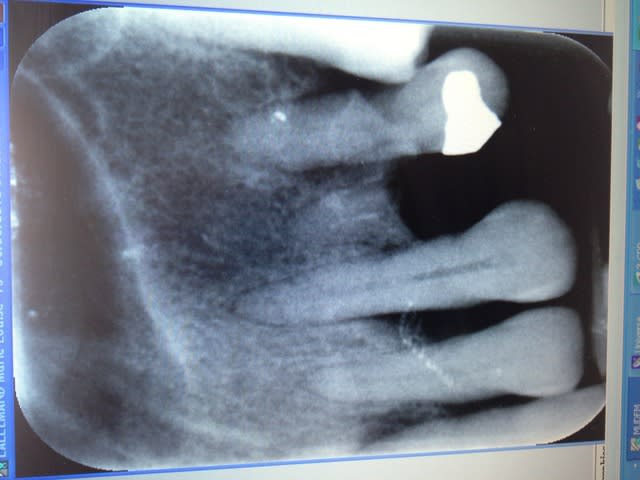

JE vous montre ce cas ou il m'est arrivé le même genre de problème.

Le patient est venue pour douleur secteur 17 que j'ai enlevé et pour refaire les deux bridges! (bridges non mobiles)

j'ai fait une chir paro secteur 20 ou j'ai constaté qu'il n'y avait plus de corticale vestibulaire j'ai donc pris la décision de couper le bridge et d'extraire 26 en lui disant qu'on ferait de l'amovible.

Retour du patient aujourd'hui il a eu très mal et est décu de devoir faire des prothèses amovible.

Je me demande si je n'aurai pas mieux fait de m'abstenir!

Voici la pano

Pour commencer, et c'est valable pour les 2 cas, il serait bon de faire tes évaluations sur un status TIB, et pas sur des panos (surtout vu leur qualité). Faire un sondage t'aurais aussi évité de perdre ton temps avec la 17.